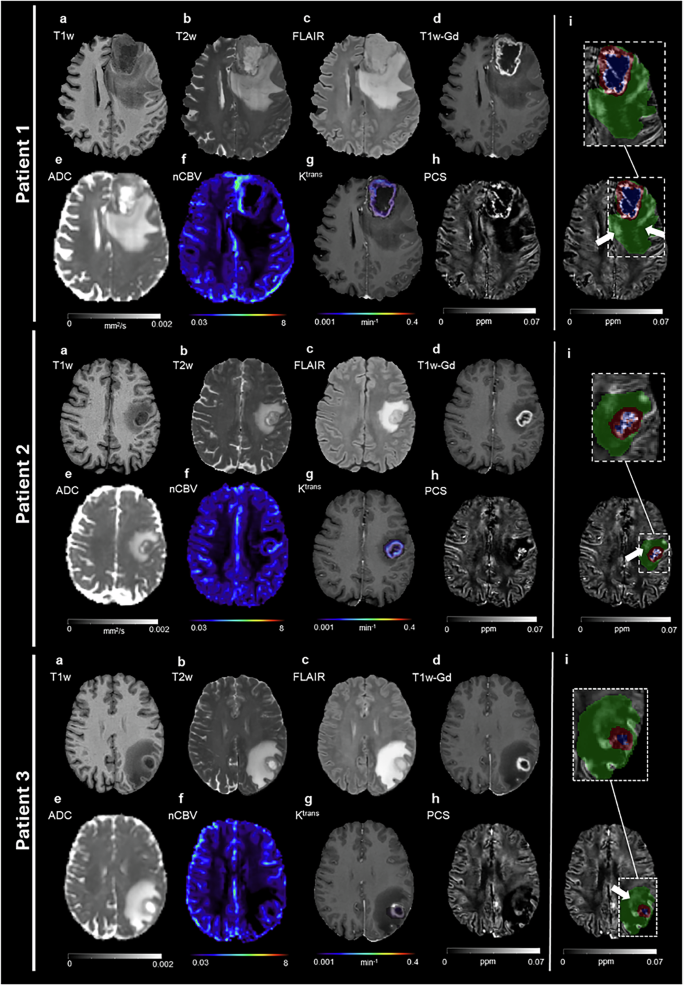

Since we were interested in the iron compound due to its altered metabolism in the tumor, we first focused on the PCS maps. Figure 1 shows MRI and derived quantitative maps from three representative patients. Structural images are used for lesion delineation (colored masks in Fig. 1i), while perfusion and permeability imaging provide blood-related information. The ADC is commonly used in clinical practice as a proxy of cellularity, but it is not specific for biological processes involving tumor and immune cells and visually it does not exhibit clear and consistent delineation of edema regions of potential high cellularity (Fig. 1e). In contrast, within the edema, regions of hyperintense PCS exhibit a striking contrast over the rest of the tissue which has low PCS values (Fig. 1h PCS only and Fig. 1i, white arrow in the green area on the PCS). This contrast is not visible on conventional MRI (Fig. 1a–e), where the edema appears generally homogeneous. This phenomenon is observed in all patients included in this study, and a representative axial slice of PCS map for each of them is reported in Supplementary Fig. 1.

Axial slices of three representative glioblastoma patients. a T1w; b T2w; c FLAIR; d T1w-Gd; e ADC; f nCBV; g Ktrans (color scale) overlapped to the T1w-Gd (gray-scale); h PCS; i PCS on top of which the color-coded lesion segmentation masks are visualized and a zoomed view (dashed rectangle) of the lesion area (green: edema; blue: necrosis; red: enhancing tissue). White arrows indicate the PCS hyperintensity in edema.

Hyperintense PCS in edema is not caused by blood